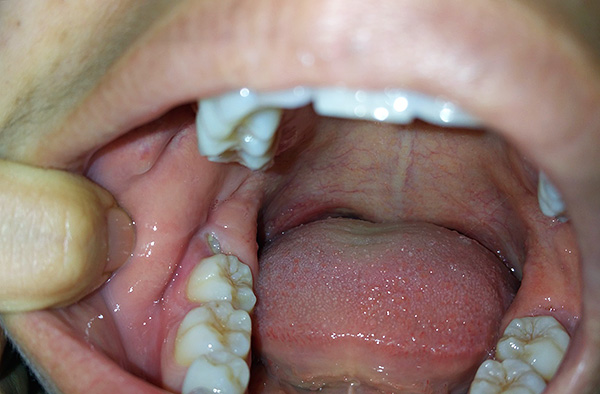

La seguente foto mostra un esempio di un dente del giudizio semi-rinforzato:

Spesso sotto il cappuccio gengivale si accumulano particelle di cibo e batteri, si verifica un processo infiammatorio: la pericoronite. Quando un essudato purulento si forma sotto la gomma, compaiono sintomi che ostacolano la normale vita di una persona: gonfiore nell'area del dente del giudizio, cattive condizioni generali, febbre fino a 38-39 ° C, incapacità di masticare e persino aprire normalmente la bocca, dolore severo, spesso pulsante e irradiante a vari sezioni del viso.